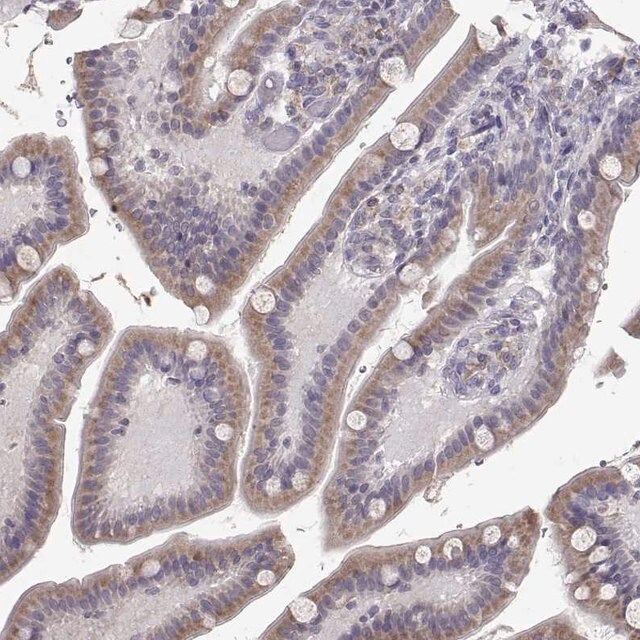

Anti-ERO1A antibody produced in rabbit

| Human Protein Atlas Number【人类蛋白质图谱编号】 | HPA026653 Human Protein Atlas characterization data |

| Immunogen【免疫原】 | endoplasmic reticulum oxidoreductase alpha |

| technique(s) | immunoblotting: 0.04-0.4 μg/mL immunohistochemistry: 1:1000-1:2500 |